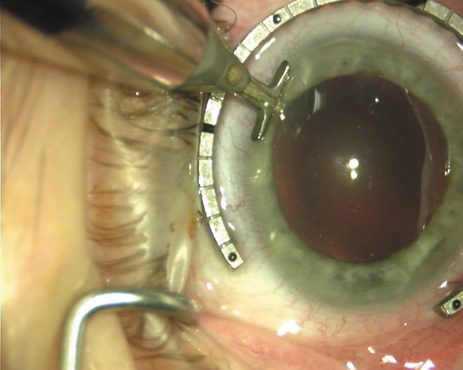

ways. Our preferred method makes use of a modified Fine-Thornton fixation

ring (Nichamin Fixation Ring and Gauge; Mastel Precision, Storz, Rhein

Medical). This instrument serves to fixate and position

the globe in order to optimize incision placement, as well as to delineate

the extent of arc to be incised. One visually extrapolates from

the limbus to marks on the surface of the ring. Each incremental mark

is 10 degrees apart, and bold hash marks (180 degrees) opposite

to each other serve to align and center the incision over the steep

meridian. This approach obviates the need to ink and physically mark

the cornea. If one desires, particularly when first gaining experience

with LRIs, a two-cut RK marker may be used to place ink marks upon the

cornea to show the exact extent of arc that is to be incised, in conjunction

with the fixation ring/gauge (Fig. 4). Alternatively, various press-on markers are available, such as

markers, rings, and blades for performing LRIs.  Fig. 4. The Nichamin Fixation Ring and Gauge serves to both fixate the globe and

delineate the extent of arc to be incised; a two-cut radial marker may

be used to mark the extent of arc to be incised, and the Mastel Nichamin

Force AK Diamond Blade with preset depth of 600 microns. Fig. 4. The Nichamin Fixation Ring and Gauge serves to both fixate the globe and

delineate the extent of arc to be incised; a two-cut radial marker may

be used to mark the extent of arc to be incised, and the Mastel Nichamin

Force AK Diamond Blade with preset depth of 600 microns.